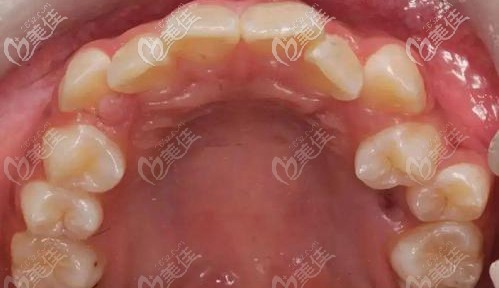

▲上個牙齒的圖片,希望不要被嚇到~